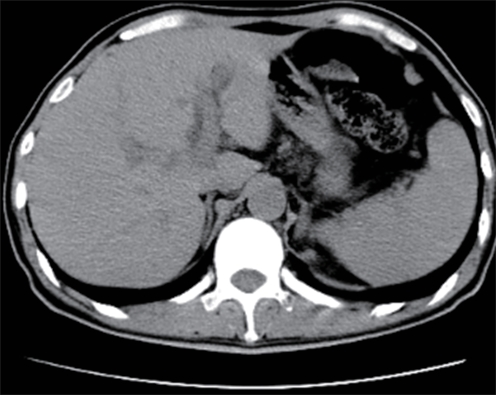

Value of internal stratification analysis of abdominal wall muscles in predicting complications after orthotopic liver transplantation

Xin SHI, Chongxiao LIANG, Bei ZHANG, Jiping WANG

2025, 41(2): 314-321. DOI: 10.12449/JCH250218

Abstract(738) HTML (351) PDF (3265KB)(53)

Abstract:

Objective  To divide the muscle into different subzones according to different density ranges using the stratified analysis on the basis of myosteatosis, and to investigate the effect of muscle density changes on complications (Clavien-Dindo grade ≥Ⅲ) after orthotopic liver transplantation (OLT).  Methods  A retrospective analysis was performed for the medical records of 145 patients who underwent OLT in The First Hospital of Jilin University from May 2013 to September 2020, and with the plain CT scan images of the largest level of lumbar 3 vertebrae of each patient as the original data, Neusoft Fatanalysis software was used to measure related muscle parameters. The independent-samples t test was used for comparison of normally distributed continuous data between two groups, and the Mann-Whitney U test was used for comparison of non-normally distributed continuous data between two groups. The chi-square test or Fisher test was for comparison of categorical data between two groups. RIAS software was used to extract clinical features and perform analysis and modeling, and three machine learning models of logistic regression (LR), support vector machine (SVM), and random forest (RFC) were constructed. The receiver operating characteristic (ROC) curve, the calibration curve, and the decision curve were plotted for each model to calculate the area under the ROC curve (AUC), sensitivity, specificity, precision, F1 score, and accuracy.  Results  The three machine learning models of LR-C, SVM-C, and RFC-C were established based on the 7 clinical features before muscle stratification analysis, among which the RFC-C model had an AUC of 0.803, a sensitivity of 0.588, and a specificity of 0.778 in the test set. Among the models of LR-CS, SVM-CS, and RFC-CS established based on the 16 clinical features after muscle stratification analysis, the LR-CS and SVM-CS models had an AUC of 0.852 in the test set, with a sensitivity of 0.765 and 0.706, respectively, and a specificity of 0.889 and 0.926, respectively. Comparison of the AUC, sensitivity, specificity, precision, F1 score, and accuracy of each model in the test set before and after muscle stratification analysis showed that there were improvements in the parameters of the predictive model after muscle stratification analysis. Comparison of the decision curves and calibration curves of each predictive model showed that the LR-CS and SVM-CS models had good efficacy in predicting postoperative complications (Clavien-Dindo grade≥Ⅲ) in OLT patients.  Conclusion  On the basis of myosteatosis, the division of the muscle into different subzones according to different densities using the stratified analysis has a certain value in predicting postoperative complications in patients with OLT.